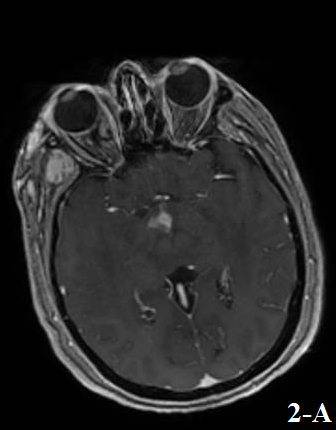

Figure 1 and Figure 2 showed the results of a brain MRI performed at admission, revealing an extensive lesion that involved the periventricular, subcortical and deep white matter.

As a major difference with PCNSL, LC lesions show poor contrast-enhancement, often presenting as ill-defined nodular, periventricular / periependymal enhancement, as what happened in our case (Kitai et al, 2012).

Figure 2. Post-gadolinium enhancement with a nodular pattern found at the level of hypothalamic area (a) and at a periventricular / periependymal level (b).